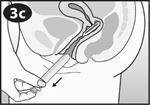

Betrachten Sie die Abbildung des Applikators um sich mit den Komponenten des Applikators vertraut zu machen. |

Fassen Sie mit Daumen und Mittelfinger den Griffbereich. |

Führen Sie das Gehäuse behutsam in die Scheide ein, bis Ihre Finger (auf dem Griffbereich) Ihren Körper berühren. |

Der Vaginalring wird aus dem Applikator gedrückt. Entfernen Sie den Applikator behutsam. |

Vergewissern Sie sich, dass sich der Vaginalring NICHT mehr im Applikator befindet. Entsorgen Sie den gebrauchten Applikator im üblichen Haushaltsabfall. Spülen Sie den Applikator NICHT die Toilette hinunter. Verwenden Sie den Applikator NICHT erneut. |